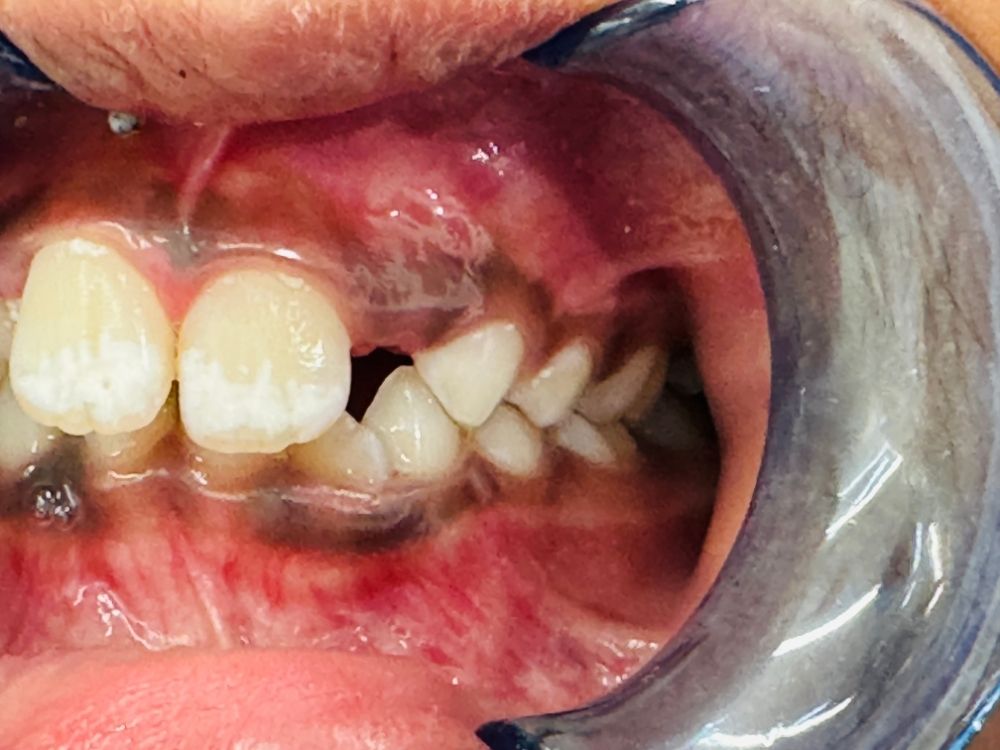

Emergencies We understand that dental emergencies can happen at any time. Whether it’s a chipped, broken, or painful tooth, our pediatric dental team is ready to provide fast, compassionate care to get your child smiling again.